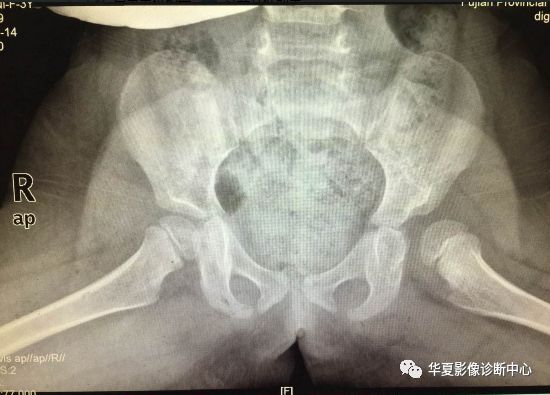

X线:

股骨头近端骨化中心出现(4~6月龄),即可推荐。

平片常规摄双髋正位和蛙式位片,典型表现包括:

①股骨头向外上移位;

②股骨头骨骺发育小、不规整,或出现延迟;

③髋臼顶发育不良呈斜坡状,髋臼角加大,可达50° - 60°;

④患侧股骨发育较细小,股骨颈短缩。

⑤骨盆:单侧脱位骨盆倾斜,双侧脱位骨盆较垂直、前倾。

⑥包绕股骨头的半弧形关节囊其上缘与髋臼顶不相接,其上方可见三角形透亮区。

上图:骨盆正位